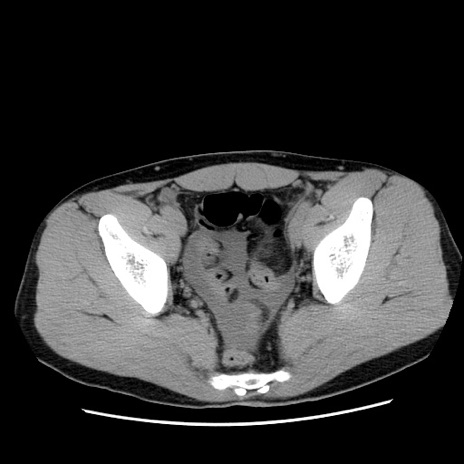

冠状断像

【症例】20歳代 男性

【主訴】心窩部痛

【現病歴】今朝より上腹部痛あり。一旦軽快していたが再度出現したため救急要請。昨日夕に白身の魚を含む刺身を食べた。

【身体所見】BP 136/89mmHg、HR 74/min、BT 37.0℃、腹部:膨満、軟、心窩部に圧痛あり。反跳痛なし、筋性防御なし、腸雑音やや亢進あり。

【データ】WBC 17700、CRP 0.48